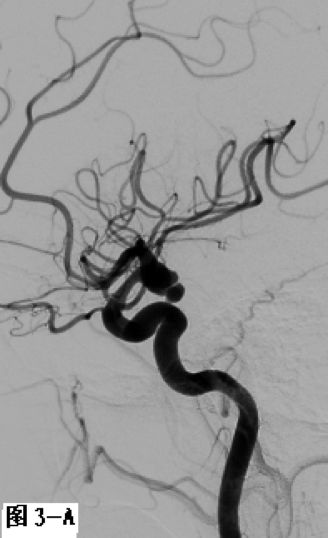

图3 采用支架辅助双微导管技术栓塞左侧颈内动脉后交通段不规则形态动脉瘤。A.DSA显示囊性动脉瘤破裂后在瘤体顶端又形成一假性动脉瘤;B.工作角度发现该动脉瘤瘤颈宽,颈内动脉直接成为瘤颈一部分;C.在部分释放支架情况下,交替填塞微弹簧圈;D.动脉瘤填塞致密,载瘤动脉通畅。